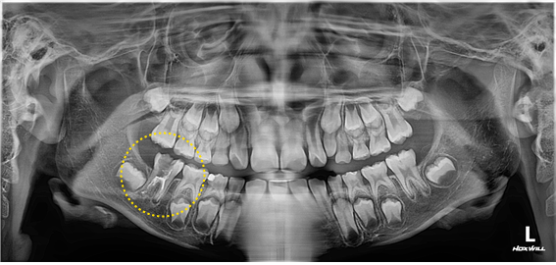

신경치료는 5번 만에 마무리 하였고, MTA를 이용한 마무리를 하였습니다.

기존 신경치료와 차이는 확연하게 느껴집니다.

그리고 한달이 지나서 재내원 하였습니다.

이미지

뿌리 끝에 있던 염증은 말끔히 사라지고, 뼈가 차고 있습니다.

증상도 없고, 보철치료를 하기로 결정하였습니다.